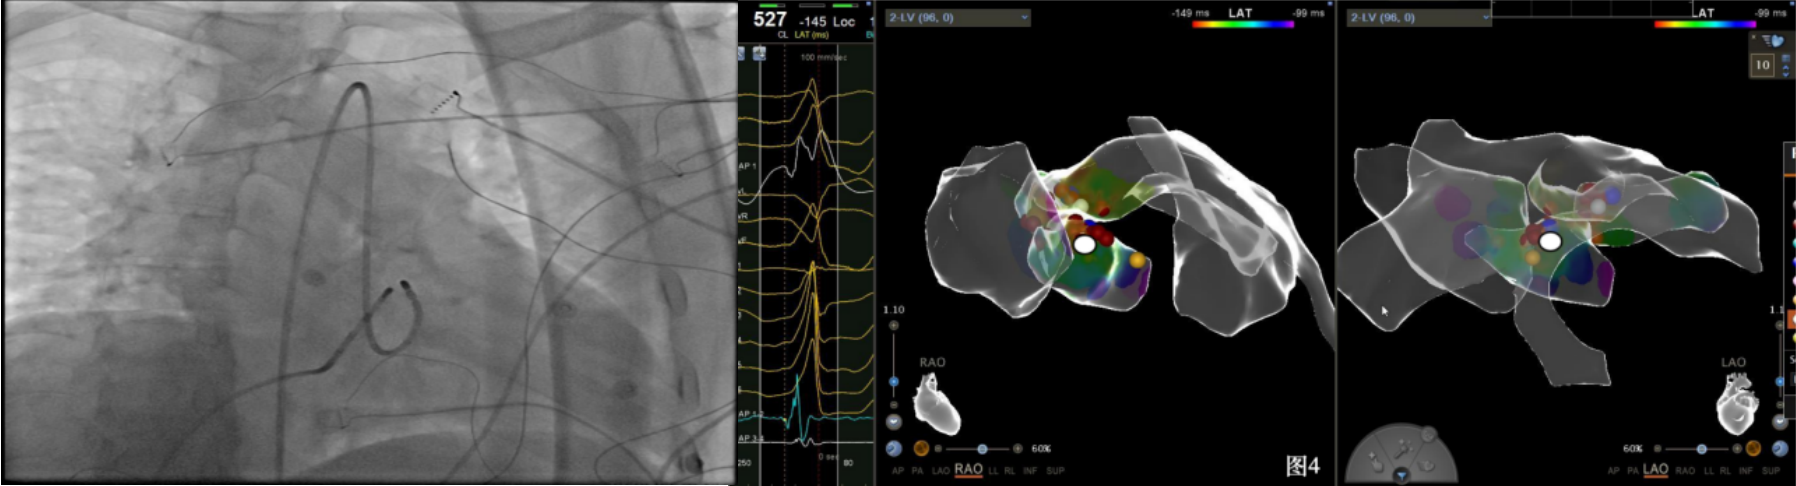

手术中,周明礼团队凭借其丰富的临床经验和精湛的技术,穿刺右股动脉后,将消融大头顺利送入主动脉,于主动脉瓣上标测到最早点(图3红色点)领先体表8ms,电位不理想,果断去到主动脉瓣下左室穹顶部标测,标测到最早点(图4白色点)领先体表25ms,放电消融3s,早搏消失,消融90s后观察2min后,早搏恢复,在该有效点周边补充消融,早搏依旧未能消失,考虑起源点较深,内膜消融未能透壁损伤到起源,随

即穿刺股静脉,将消融大头送至冠状窦内,在GCV远端对应位置标测到最早点(图5绿色点)领先体表27ms,消融后早搏未能消失,周明礼评估起源点偏心外膜,能量依旧不能穿透损伤到起源点,内膜消融基本无效后,果断选择难度系数最为复杂的干性心包穿刺心外膜消融。在导丝的指引下,将消融大头送至心包层(图6),于外膜标测到靶点(图7黄色点)电位领先体表31ms,单极电位无r波且有顿挫,ssummit外膜离冠状动脉较近,比较危险,保证安全,进行了冠脉造影(图7),显示距离LAD和LCx有一定距离,相对安全,随即放电,2s室早消失,10s患者出现心率变慢,该区域走形迷走神经节,消融导致心率减慢,随后保证心率正常的情况下,消融够60s,随后观察半小时,早搏没有恢复,手术成功(图8)。经过不懈的努力,患者恢复了窦率,心脏功能也逐渐恢复正常,手术取得了圆满成功。